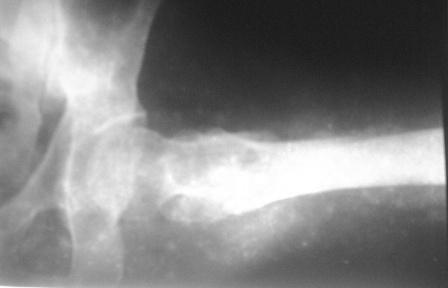

Больному 50л. В отдаленном от центра р-не ДТП 6.12.08г. д-з " тяжелая ЧМТ, мн.перломы ребер слева,отрыв ножки селезенки, повреждение п/ж железы, з/двойной перелом прав.бедра.

После экстрен. хирургических вмешательств, конечность фиксирована кокситной гипсовой лонгетной повязкой. Кома 2 нед, нагноение п/о раны живота, посттравмат. пневмония. 20.01.09г. переведен к нам. Постельный больной, ослабленный,бледный, весом 56кг: свищ п/о раны перед. брюшной стенки с сукровичным выделением, гипс снят - деформация и укорочение бедра на 6 см, в обл перелома есть спайка. слабо, но активно поднимает ногу, контрактура т/б и коленных суставов. Обшеукреп. лечение, компоненты крови, общ. массаж, ЛФК и больной активизирован, начал ходить с костылями, движения в суставах почти восстановлены. НВ-112, эр-3,5млн. Наш план блокир. и/м остеосинтез. Имеется гвозди для ВНПБ ЦИТО, но PFN не имеется

Лучше сделать остеоклазию на уровне диафиза секциями аппарата (ротацией), затем проводить дистракцию темпом 2-4 мм/сут дробно, в пределах переносимости пациентом. После восстановления длины и сопоставления диафиза по оси закрыто заштифтовать. Имеющийся стержень вполне подойдет, поскольку вертельный перелом уже не будет требовать остеосинтеза.